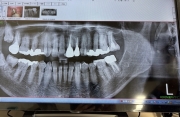

CTの画像は撮ってもらえた医院のを持参して診てもらいました。

今日1/21 CT撮影してもらった歯科医院を受診し、CT画像を見ながら相談しました。